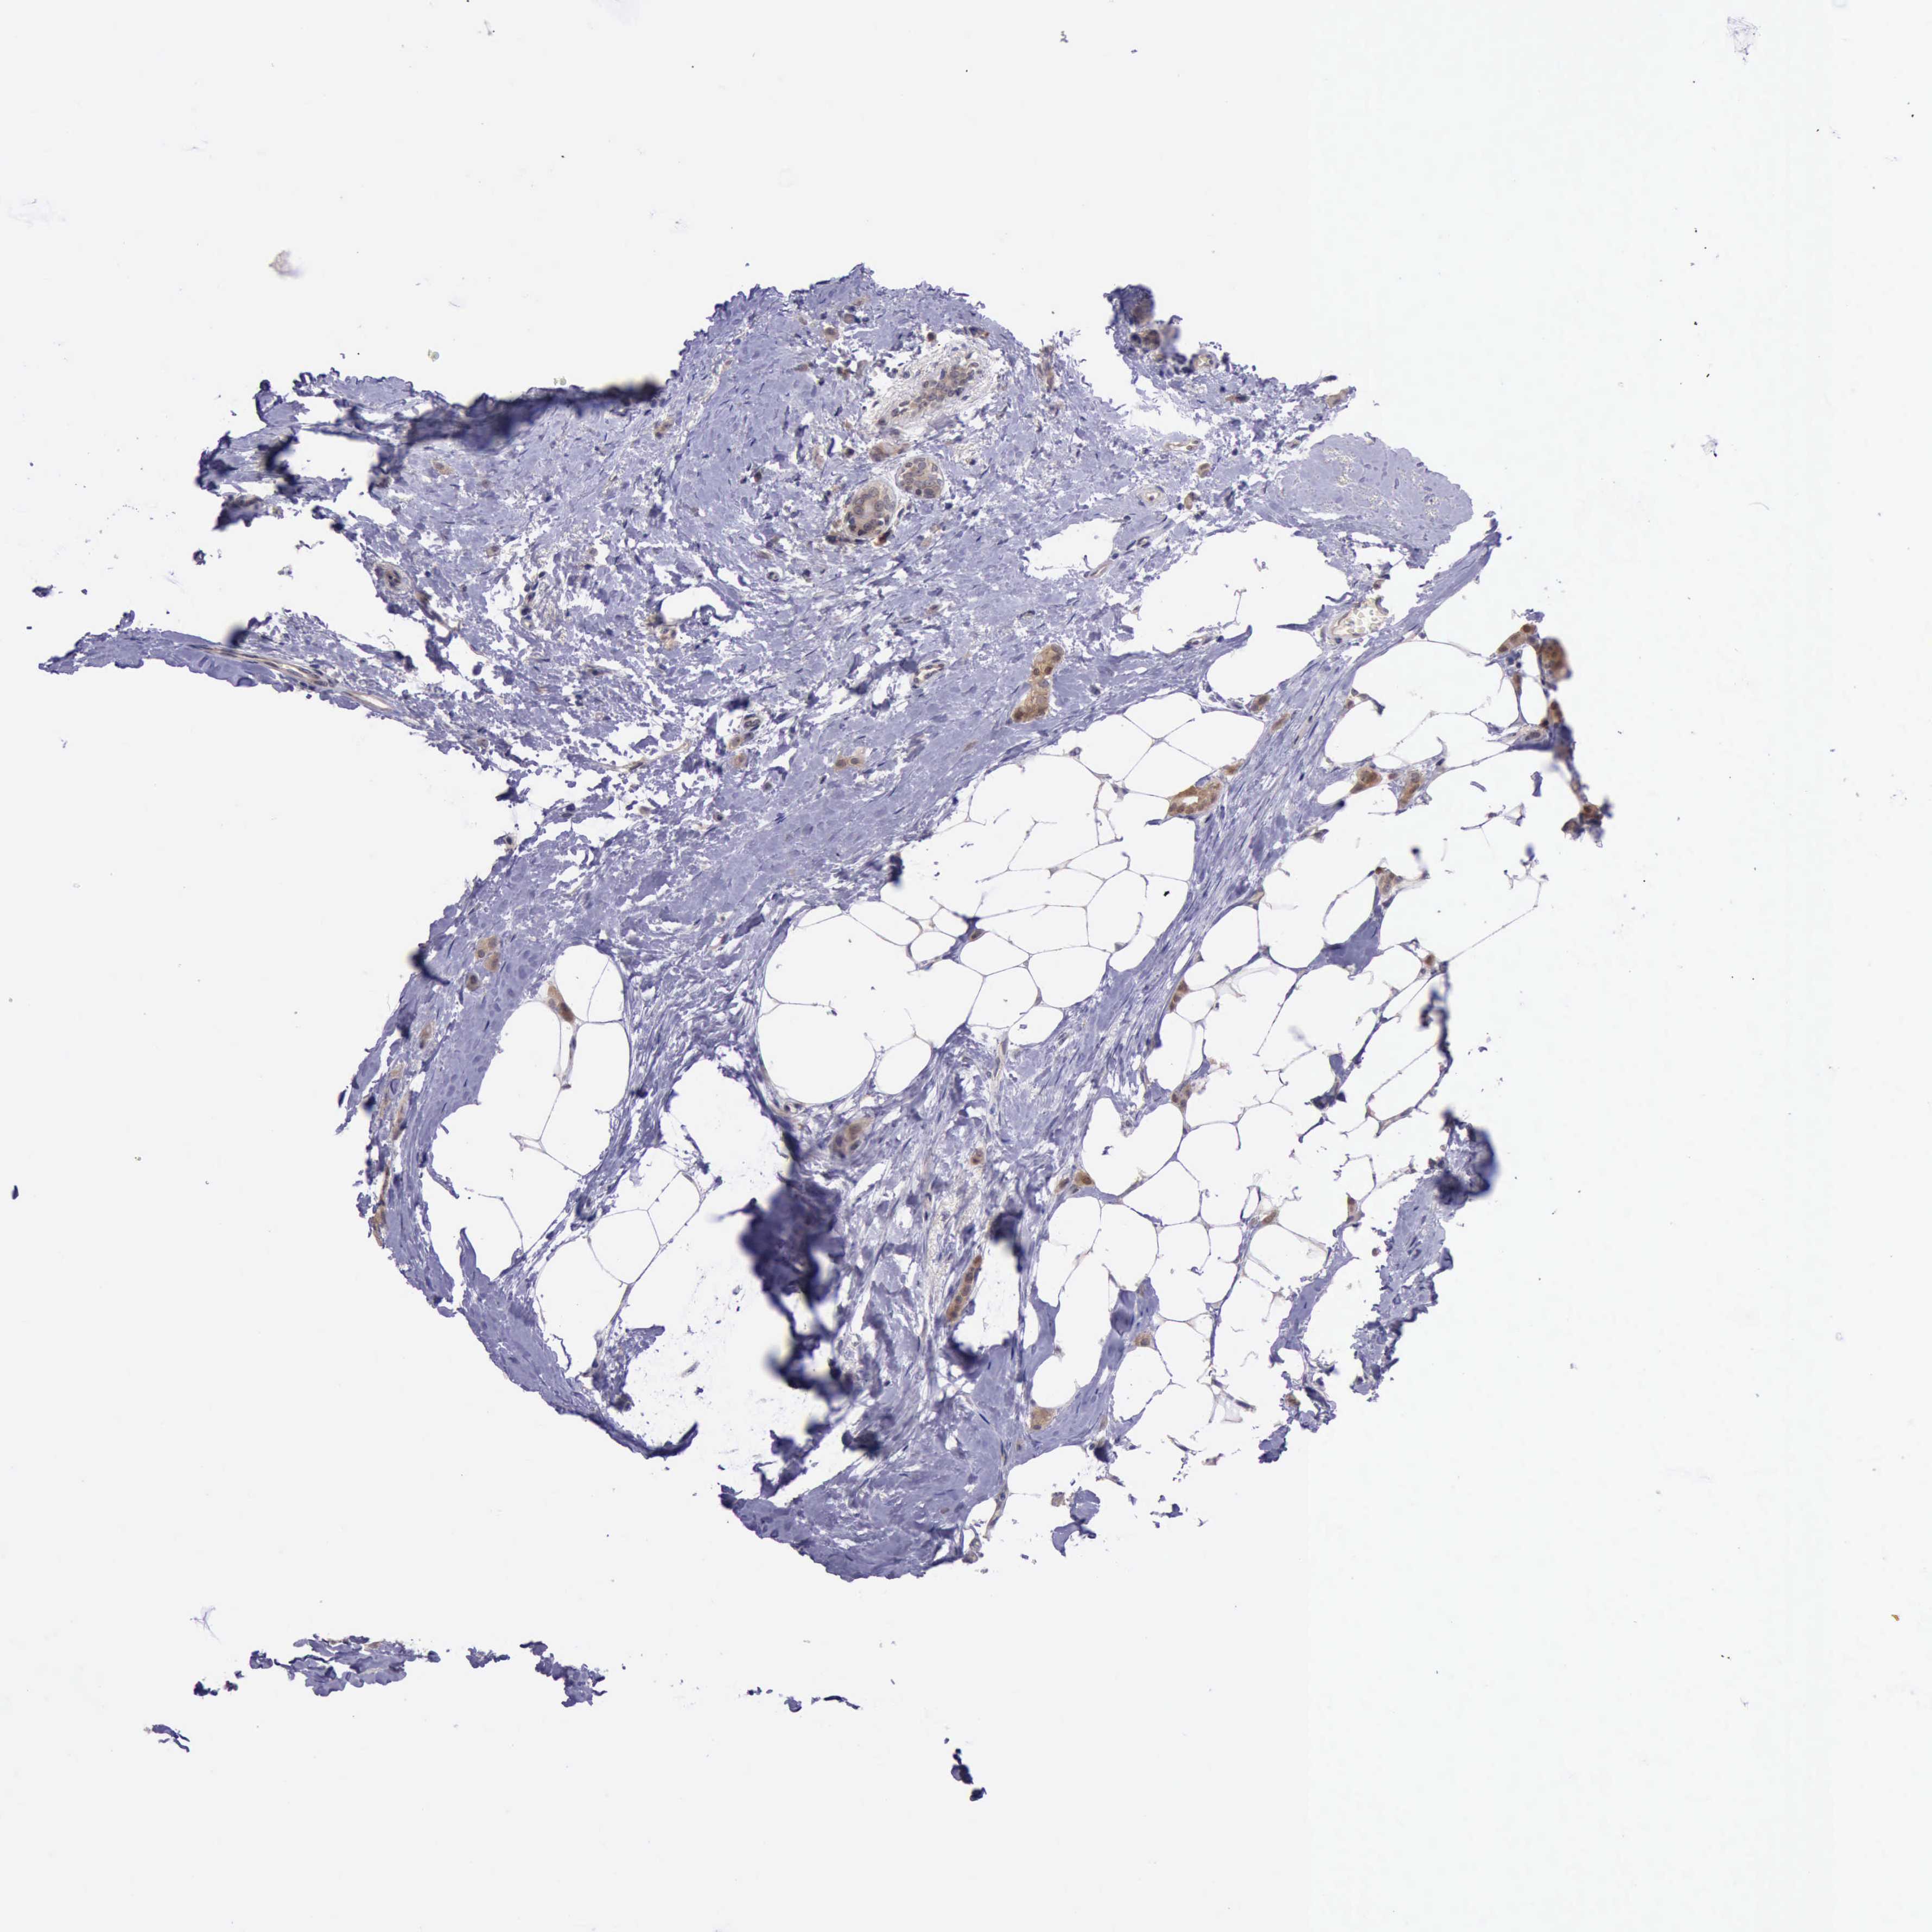

CANCER BREAST CANCER Show tissue menu

BRCA TCGA BRCA VALIDATION PROTEIN EXPRESSION

Breast cancer

Human cancer

Breast invasive carcinoma